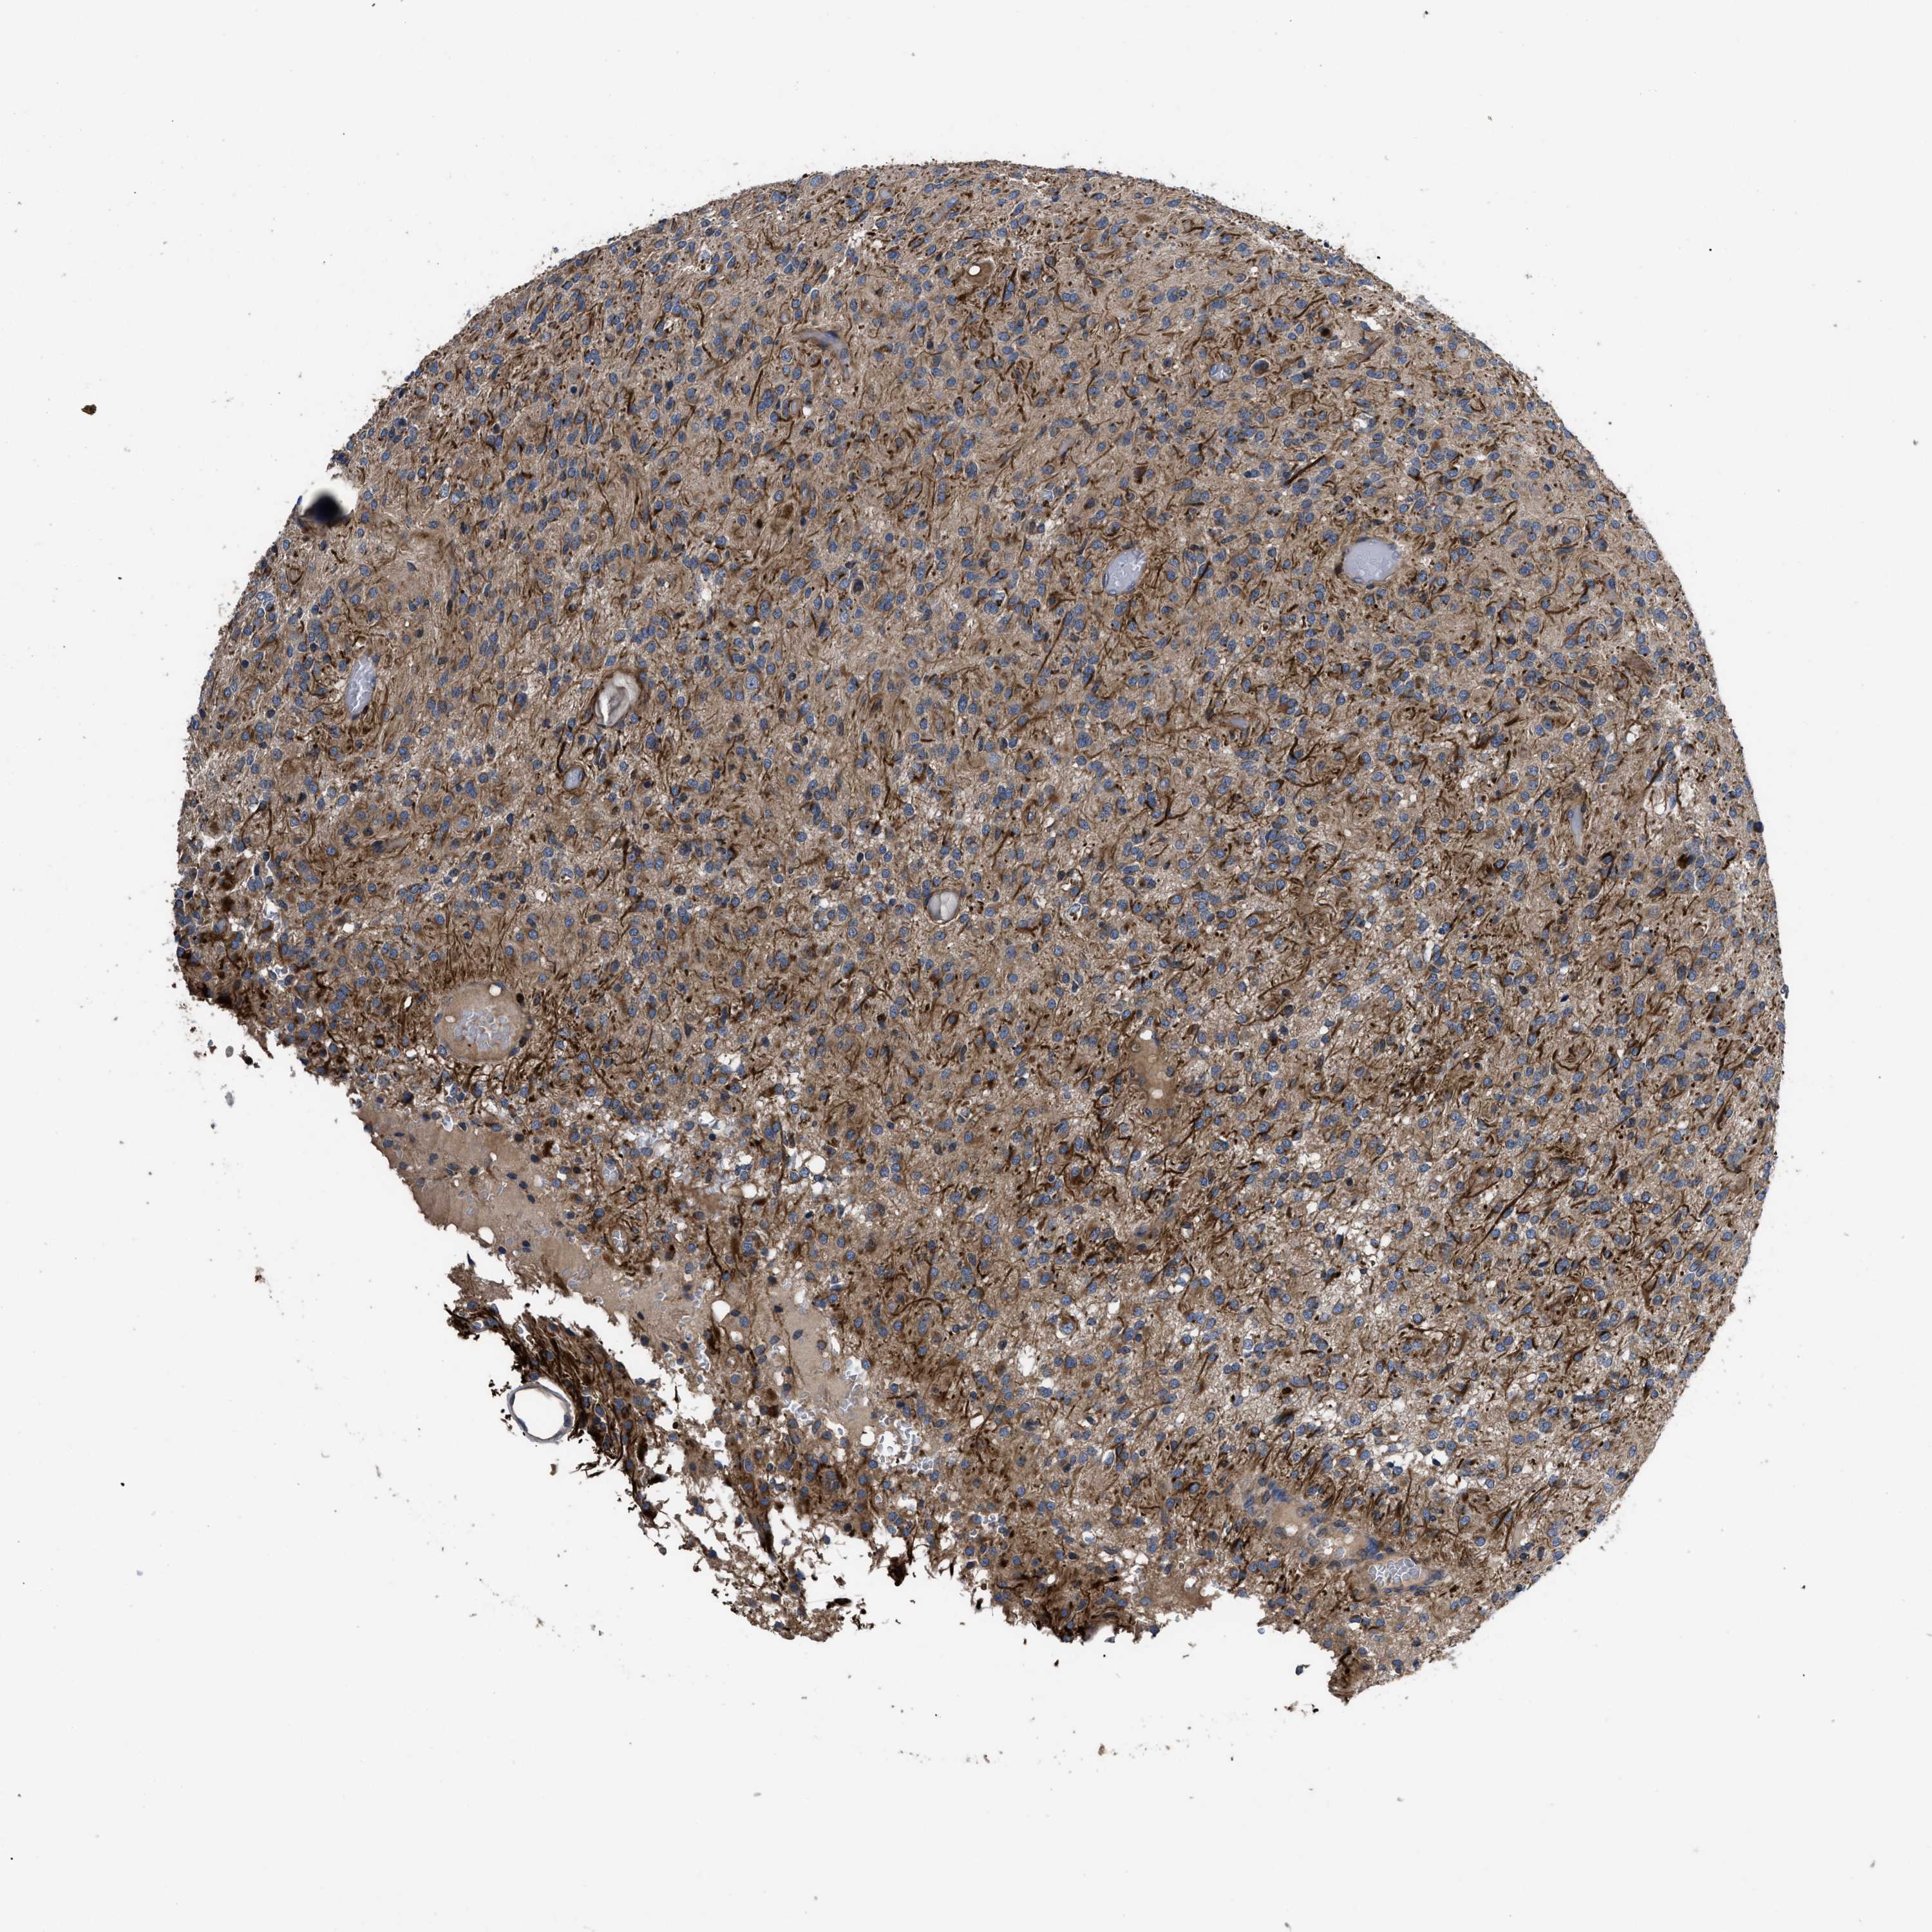

GLIOMA - Protein expressioni

A mouse-over function shows sample information and annotation data. Click on an image to view it in a full screen mode. Samples can be filtered based on level of antibody staining by selecting one or several of the following categories: high, medium, low and not detected. The assay and annotation is described here.

Note that samples used for immunohistochemistry by the Human Protein Atlas do not correspond to samples in the TCGA dataset.

Antibody stainingi

Antibody staining in the annotated cell types in the current human tissue is reported as not detected, low, medium, or high, based on conventional immunohistochemistry profiling in selected tissues. This score is based on the combination of the staining intensity and fraction of stained cells.

Each image is clickable and will lead to virtual microscopy that enables deeper exploration of all samples and also displays staining intensity scores, fraction scores and subcellular localization as well as patient and tissue information for each sample.

Antibody HPA018162

Staining

High

Medium

Low

Not detected

Intensity

Strong

Moderate

Weak

Negative

Quantity

>75%

75%-25%

<25%

None

Location

Nuclear

Cytoplasmic/membranous

Cytoplasmic/membranous,nuclear

Glioma, malignant, High grade

Glioma, malignant, Low grade